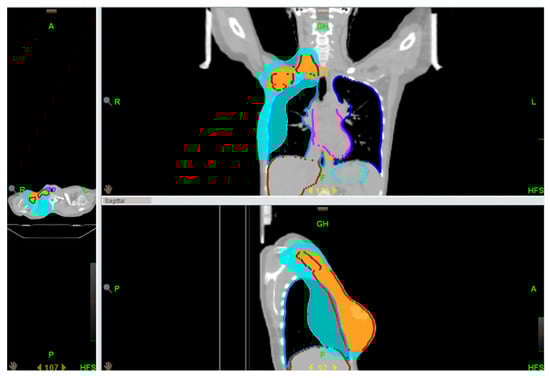

2.1. Radiotherapy Treatment Technique

3.1. Plans Evaluation